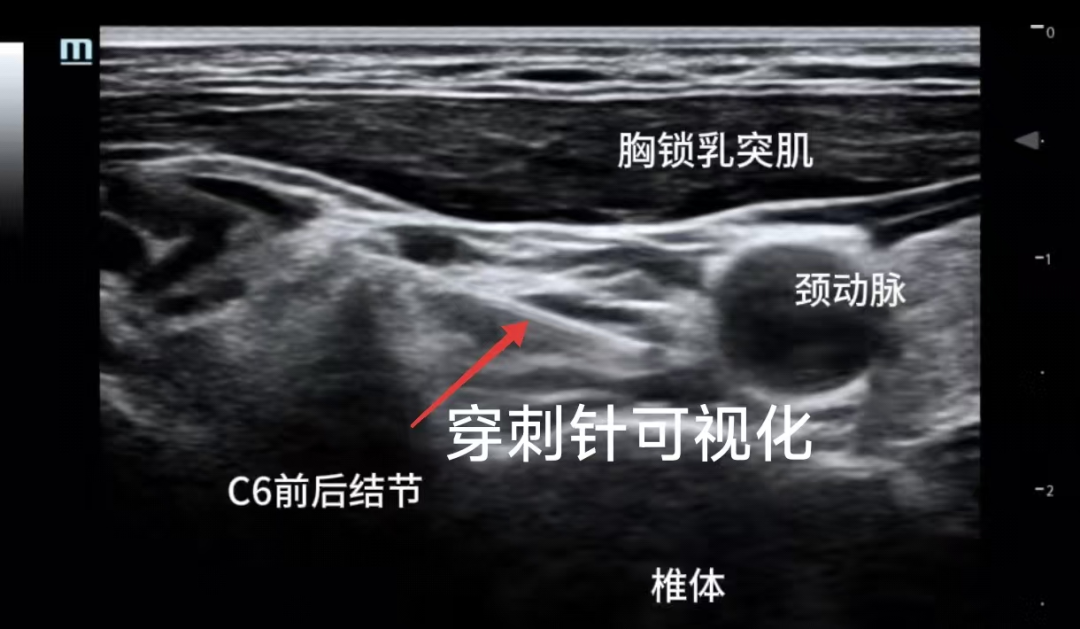

超声可视化,更加精准安全

疼痛门诊采用的超声可视化星状神经节阻滞技术与传统盲探穿刺方法相比,实现了超声引导可视化操作。

医生能够实时观察穿刺针的位置和药液扩散情况,精准地将药物送达目标区域,同时有效避开血管、神经等重要结构,减少了并发症风险,为患者提供了更加安全有效的治疗选择。